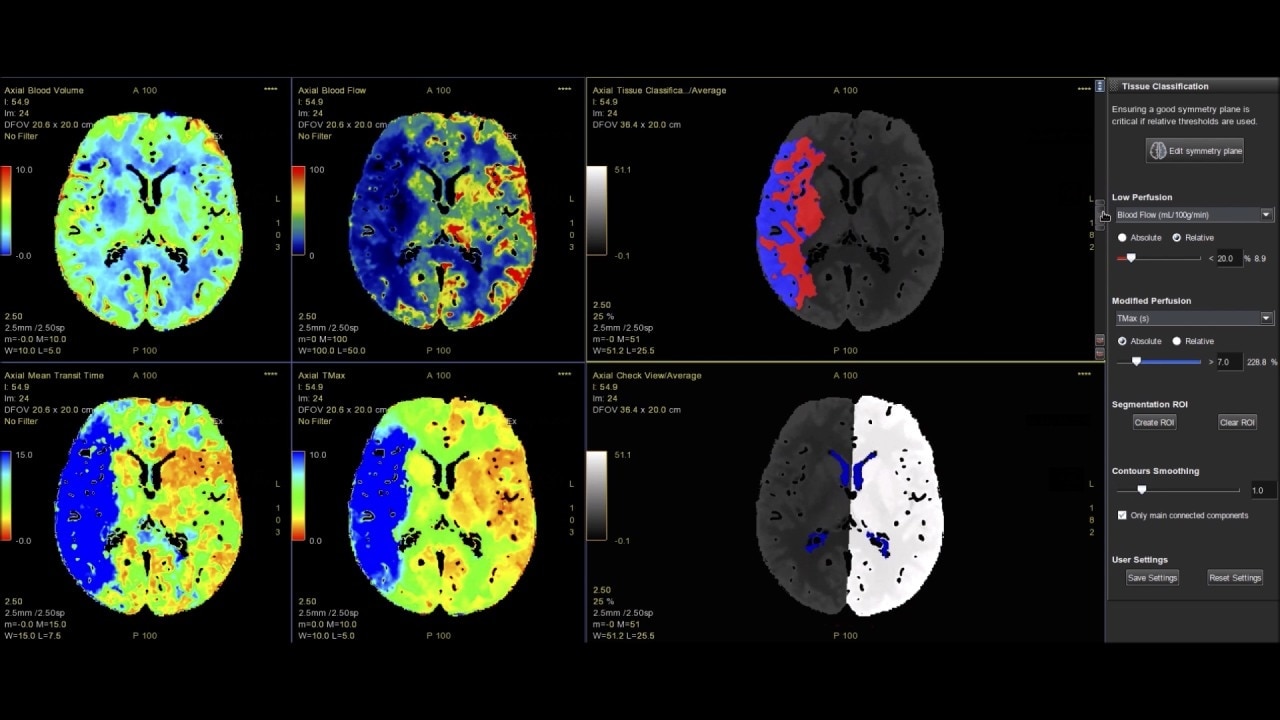

Brain perfusion

Easy-to-use automated workflow for CT stroke and tumor angiogenesis evaluation